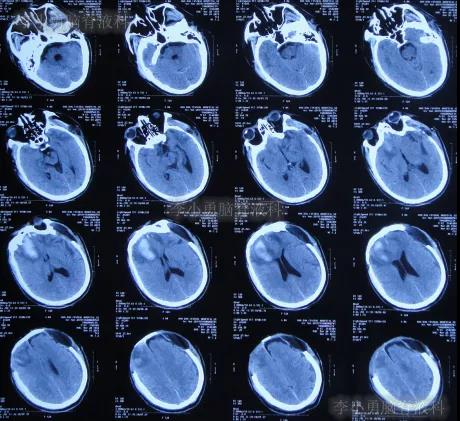

但第1家医院出院后13天即2019年12月4日,出现尿失禁,到当地的邯郸市临漳县某医院查头颅CT(图-13)后,转给给予开颅手术的医院医生,医生认为与出院时无明显变化,但之后的6天时间内出现走路不稳,大小便失禁加重的症状。

图-13:2019年12月4日头颅CT

为求进一步有效治疗,于第1家医院出院后19天即2019年12月10日,住入第2家的北京某解放军的三甲医院,入院次日查头颅CT(图-14)后认为是脑积水。

图-14:2019年12月11日头颅CT